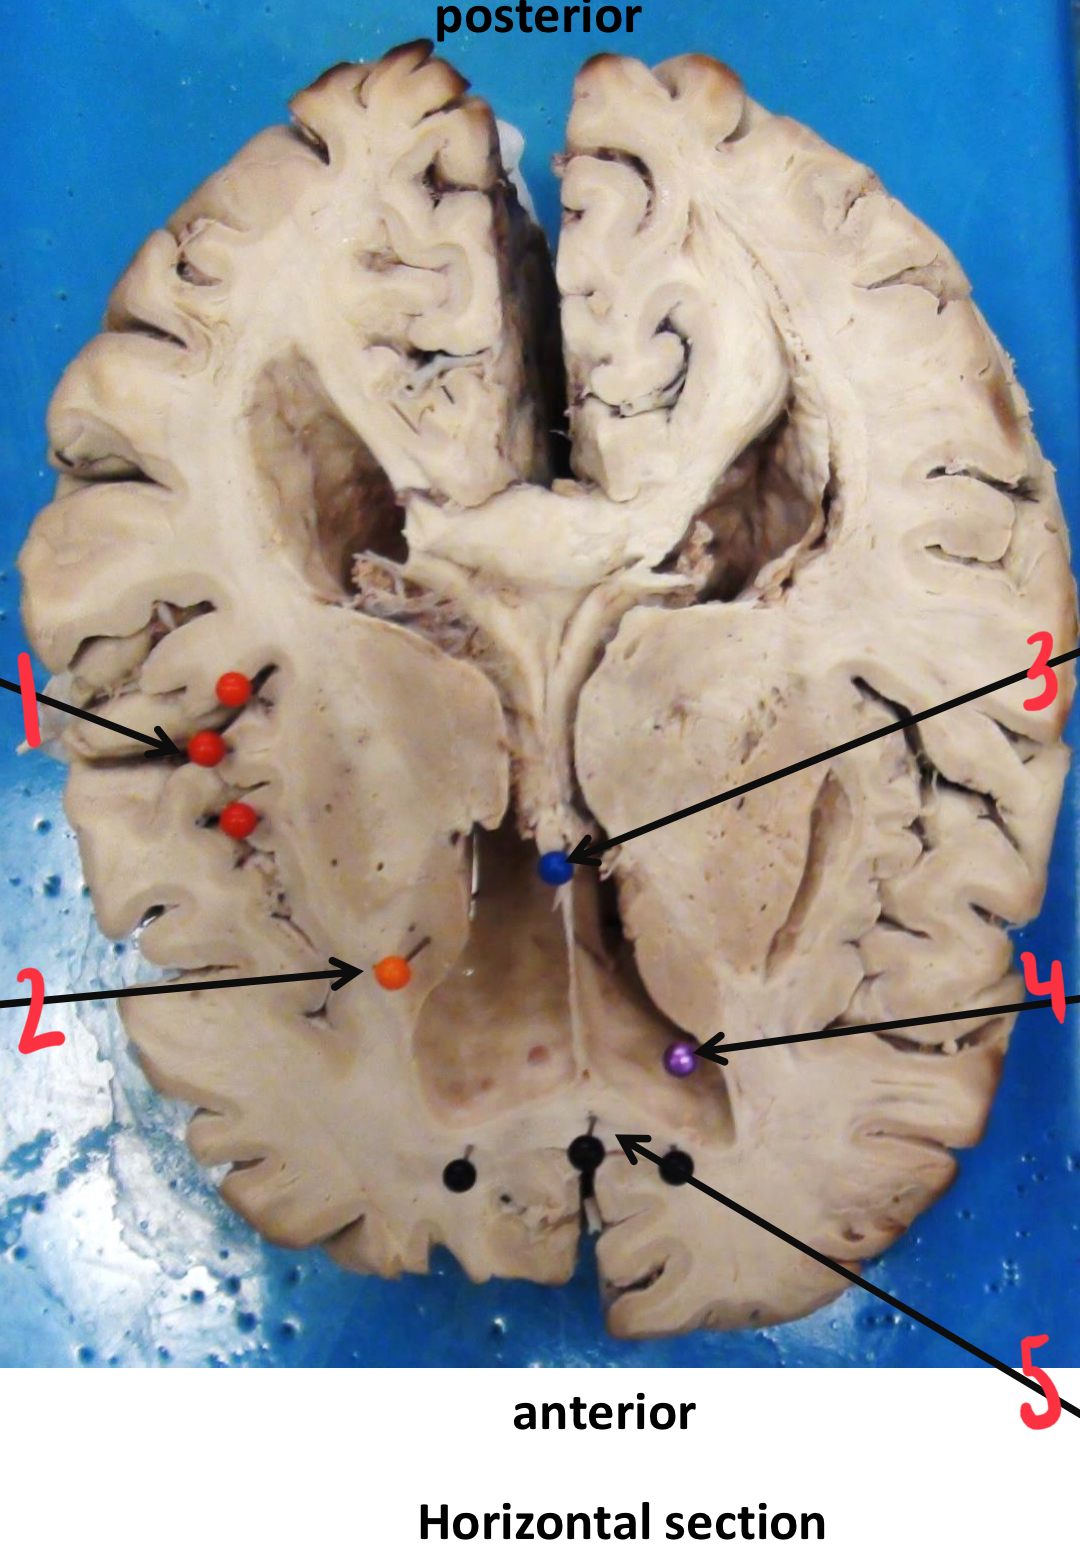

1

choroid plexus

2

pineal gland

3

lenticular (lentiform) nucleus

4

thalamus

5

internal capsule

6

septum pellucidum